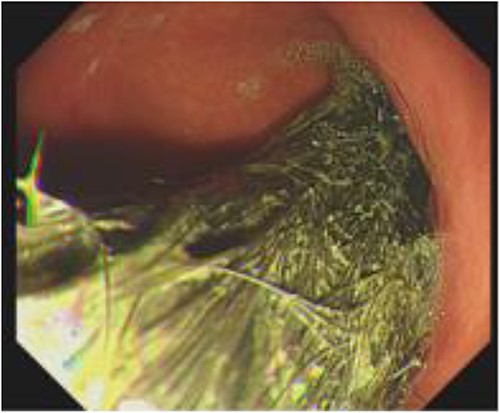

The patient underwent a gastroscopy which confirmed a large trichobezoar in the stomach with a tail extending into the duodenum (as seen in Fig. 2) and subsequently underwent laparoscopic gastrotomy for the removal of the trichobezoars. Laparoscopically an incision in the anterior wall of the stomach was performed and both trichobezoars were manipulated and delivered through the same gastrotomy (as seen in Fig. 3).

Gastroscopy image showing the presence of hair fibres forming the trichobezoar in the stomach.